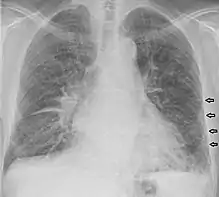

Kerley lines

Kerley lines are a sign seen on chest radiographs with interstitial pulmonary edema. They are thin linear pulmonary opacities caused by fluid or cellular infiltration into the interstitium of the lungs. They are named after Irish neurologist and radiologist Peter Kerley.[1][2]

Kerley B lines

These are short parallel lines at the lung periphery. These lines represent interlobular septa, which are usually less than 1 cm in length and parallel to one another at right angles to the pleura. They are located peripherally in contact with the pleura, but are generally absent along fissural surfaces. They may be seen in any zone but are most frequently observed at the lung bases at the costophrenic angles on the PA radiograph, and in the substernal region on lateral radiographs.[3] Causes of Kerley B lines include pulmonary edema, lymphangitis carcinomatosa and malignant lymphoma, viral and mycoplasmal pneumonia, interstitial pulmonary fibrosis, pneumoconiosis, and sarcoidosis. They can be an evanescent sign on the chest x-ray of a patient in and out of heart failure.